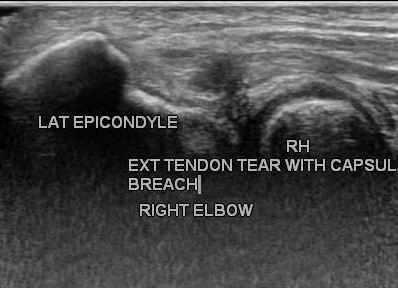

Previous ImageNext Image lateral-epicondylitis-tear-with-capsular-breach EXTENSION OF TEAR TO THE CAPSULE OF JOINT